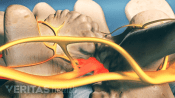

Injections relieve neck and back pain by delivering medications directly to the affected area, reducing inflammation.